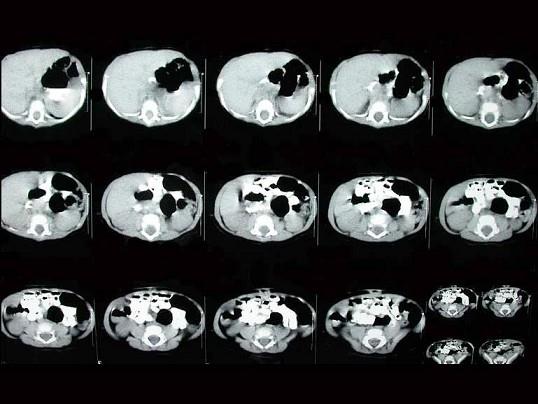

女,5岁,食欲差伴消瘦4年。如图所示,最可能的诊断为?(?)A.食道裂孔疝B.膈疝C.肺脓疡D.包裹性液气胸E.胃扭转

问题 女,5岁,食欲差伴消瘦4年。如图所示,最可能的诊断为?(?)

选项 A.食道裂孔疝 B.膈疝 C.肺脓疡 D.包裹性液气胸 E.胃扭转

答案 A